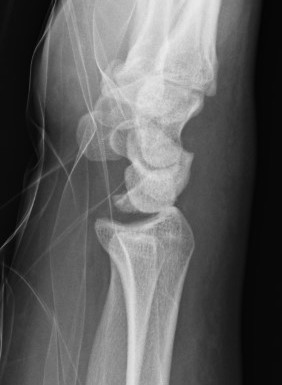

Xray

Dorsal radiocarpal dislocation with dorsal rim fracture

Dorsal radiocarpal dislocation with radial styloid fracture